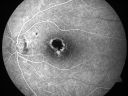

OS: Vertical C/D ratio is 0.2. There is a partial posterior vitreous separation. There are trace vitreous cells, which look to be old. There is a plaque chorioretinal scar just on the superior edge of the fovea as well as a tiny scar superonasal to that.

FLUORESCEIN ANGIOGRAPHY: Fluorescein angiography shows predominately hypofluorescence where the toxoplasmosis scar is centrally with some hyperfluorescence around the edge, which fades in the late frames.